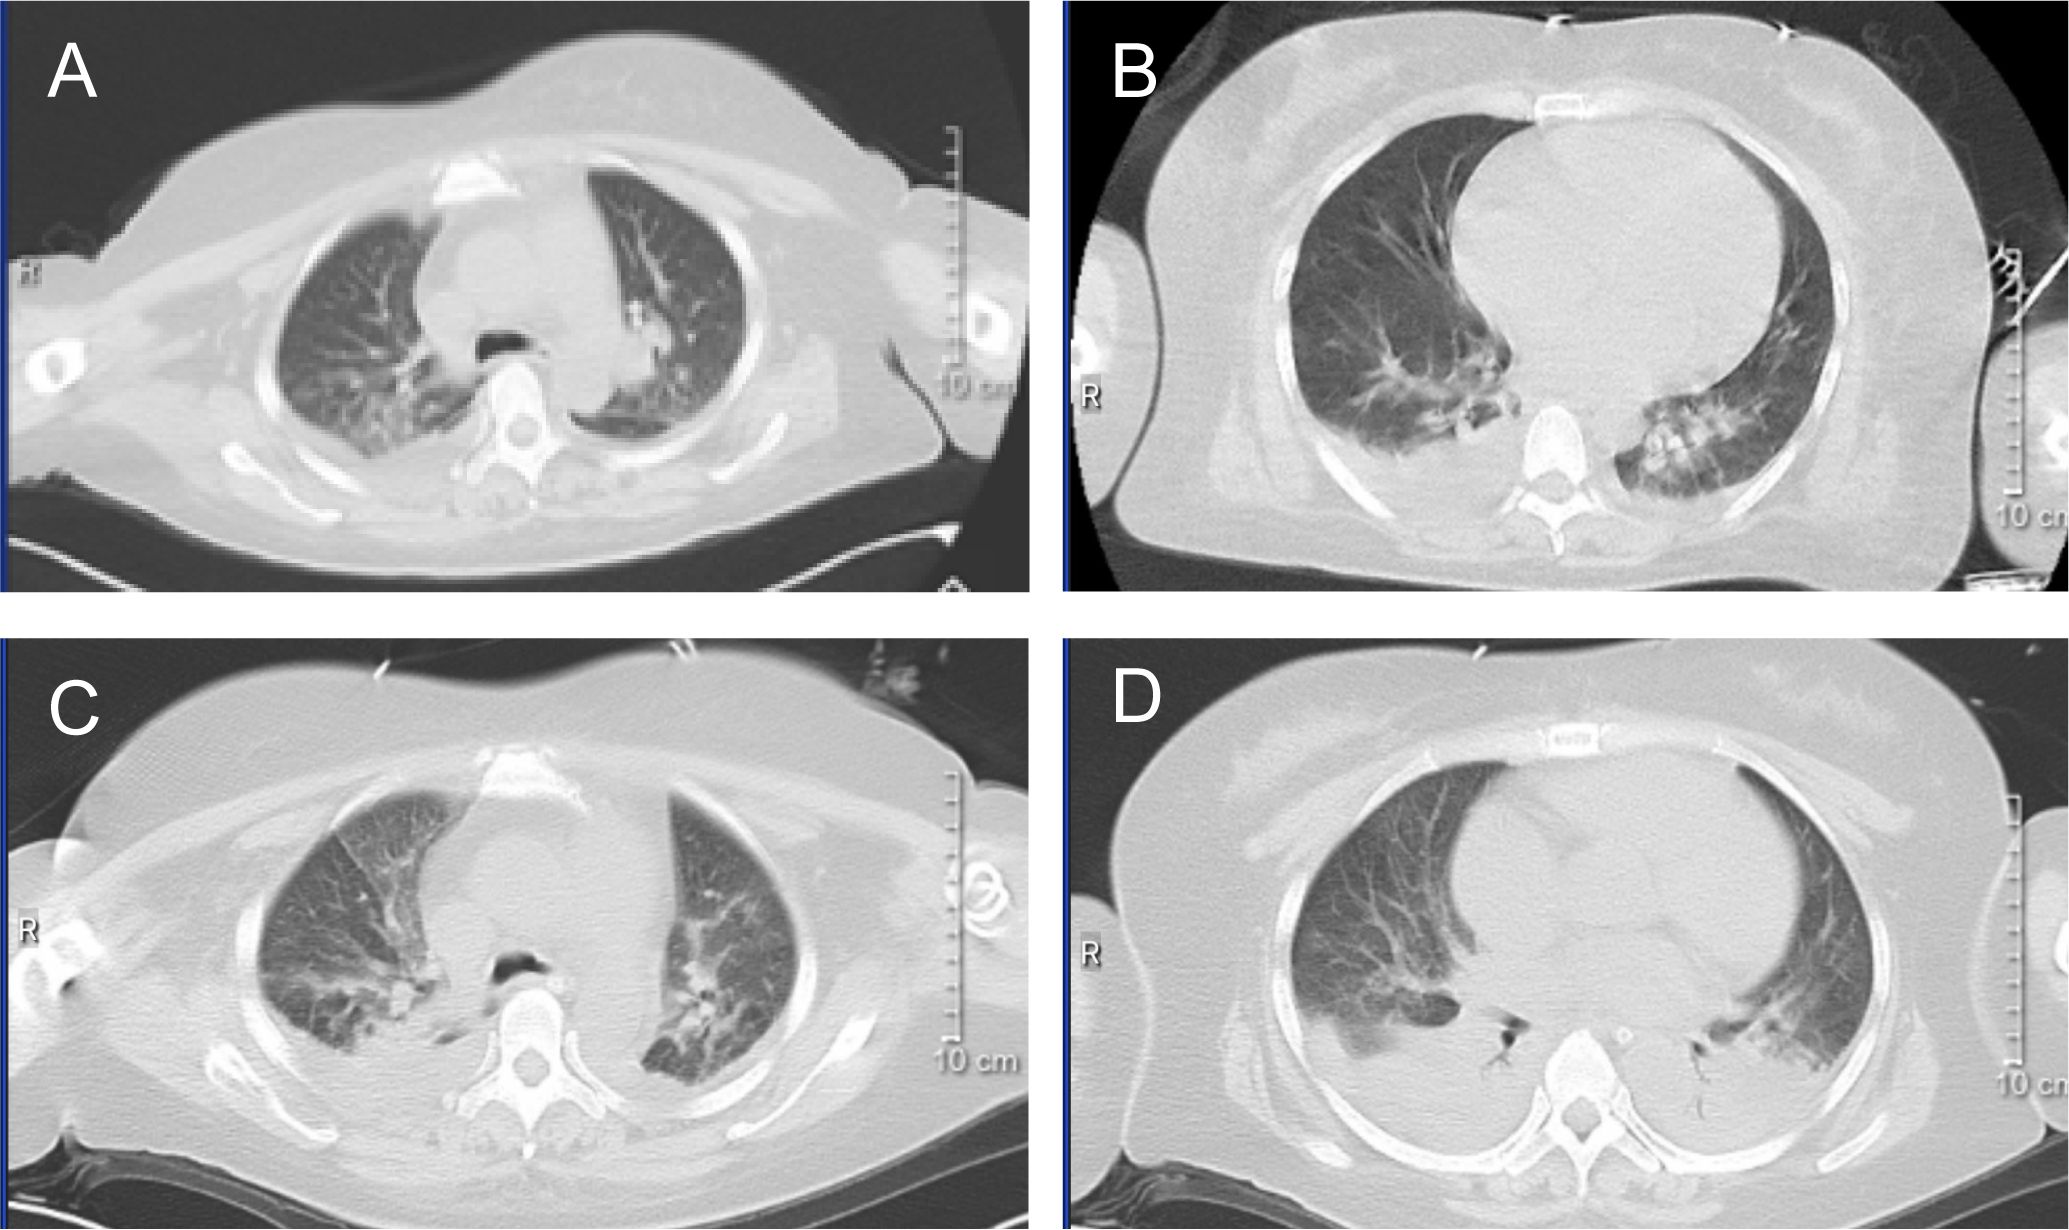

On February 26, the WBC were 12.24×109/L, and on February 27, they increased to 17.59×109/L. A rapid rise in leukocytes often signals the onset of DS. ATRA and RIF were immediately stopped. Given the patient’s lengthy history of schizophrenia, glucocorticoids may worsen the patient’s psychosis. Due to the patient’s lack of cooperation, the use of deep vein cannulation to administer conventional chemotherapy medications to achieve cytoreduction seemed to be extremely challenging. By 6:00 a.m. on February 28, laboratory tests revealed that WBC had increased to 22.91×109/L and procalcitonin (PCT) was 23.17ng/ml. She also experienced dyspnea, chest distress, and palpitation, which prompted us to administer hydroxyurea 1g three times a day, meropenem for antibacterial therapy, and fluconazole as fungal prophylaxis. The Computed Tomography (CT) scan revealed pulmonary edema in both lungs, pulmonary infection, pleural effusion on both sides, and pericardial effusion (Figures 2A, B). The patient’s dyspnea worsened at 8:50 p.m. on February 28 and could not be alleviated by oxygen uptake. The patient unexpectedly experienced heart arrest and loss of consciousness at 21:00. Cardiopulmonary resuscitation (CPR) was done immediately by physicians and nurses, and the patient’s spontaneous heartbeat and respiration returned 5 minutes later, but her consciousness remained in a mild coma. The WBC was up to 47.89×109/L, LDH 6250 U/L, plasma B-type natriuretic peptide (BNP) > 35000 pg/ml, Alanine Aminotransferase (ALT) 111 IU/L, and Aspartate Aminotransferase (AST) 299 IU/L. Cerebral bleeding was ruled out by CT scanning. For advanced life support, the patient was moved from the hematological ward to the intensive care unit (ICU). Given that hydroxyurea was ineffective in cytoreduction, we stopped it. We administered ruxolitinib 10 mg twice daily to ameliorate the cytokine storm syndrome and venetoclax 20 mg once daily for cytoreduction. On February 29, the WBC was 72.16×109/L; on March 1, it was 68.51×109/L; and on March 2, it fell to 23.96×109/L. On March 3, it decreased to 5.19×109/L, and venetoclax was suspended. The patient’s coagulation disorder was controlled during this period by receiving transfusions with fresh plasma, platelets, and red blood cells. After reaching a peak of 9181 U/L, LDH steadily dropped, ALT and AST returned to normal, and creatinine dropped from 573 μmol/L to 134.8 μmol/L. In the peripheral blood smear, the promyelocyte percentage dropped from 92% to 0. However, the PCT rose from the initial 3.34 ng/ml to 23.17 ng/ml and peaked at 70.63 ng/ml, and her temperature was consistently higher than 38°C. A novel hemorrhagic lesion marked by subarachnoid hemorrhage (SAH) was indicated by cranial CT. Bilateral pleural effusion and inflammation in the upper lobes of both lungs were revealed by chest CT (Figures 2C, D). Subcutaneous edema, abdominopelvic effusion, and perirenal exudate in both kidneys were indicated by abdominal CT. Candida albicans was discovered in the patient’s sputum cultures, whereas fungi were suggested by blood cultures. The patient was treated with meropenem, linezolid, voriconazole, and caspofungin. The patient’s temperature progressively dropped to 37.5°C, and the PCT fell from a high of 70.63 ng/ml to 9.21 ng/ml. SAH and bilateral pleural effusions were still suggested by CT on March 5. Laboratory test revealed WBC 1.84×109/L, hemoglobin 82 g/L, platelets 57×109/L, fibrinogen 4.39 g/L, creatinine 121 μmol/L, ALT 71 IU/L, and AST 41 IU/L on March 9, when the patient’s temperature had returned to normal. We restarted ATO 10 mg once daily and ATRA 10 mg three times daily. On March 11, the patient reemerged unexpectedly with a temperature of 39°C, hematochezia, and hematuria. Tests showed WBC 2.51×109/L, hemoglobin 53 g/L, platelets 4×109/L, fibrinogen 6.03 g/L, and creatinine 143.7 μmol/L. We suspended ATRA and ATO, administered ambulatory blood pressure monitoring, red blood cells and platelets transfusion, and treated the hematochezia and hematuria. On March 12, around 21:20, the cardiac monitor showed that the heart rate had decreased to 22 beats per minute and the blood pressure had dropped to 75/31 mmHg. The physicians and nurses performed CPR immediately, but the patient failed to regain spontaneous heartbeat and respiration and was declared clinically dead at 22:00. Two days later, the patient’s sputum culture revealed Ralstonia mannitolilytica, while the blood culture revealed Enterococcus. Figure 3 displayed the changes of WBC, hemoglobin, platelets, fibrinogen, PCT, and the proportion of promyelocytes in the peripheral blood smear.

Figure 2. CT image. (A, B) the chest CT image of February 28, 2024. (C, D) the chest CT image of March 3, 2024.